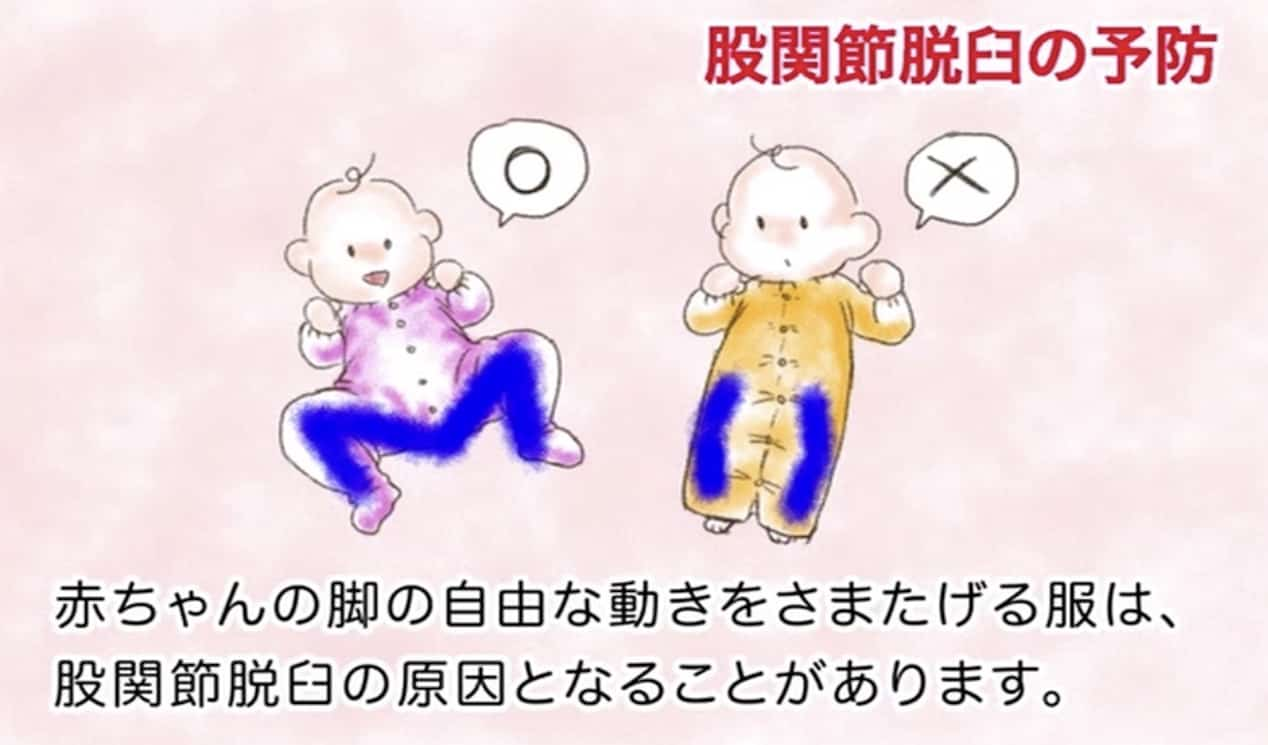

間違った育て方とは(環境因子)

① 股・膝関節を強く伸ばして筋肉を緊張させる。

② 股関節を固定して自由に動けなくする。

この2つがあてはまるような育て方をすると脱臼しやすくなります。単殿位の逆子に脱臼が多いのは①が原因です。おむつの種類や付け方、服の選び方、抱っこのしかた、向き癖への対処などが重要です。詳しくは「脱臼しない育て方」をご参照下さい。

脱臼しない育て方

出生直後の股関節は、臼蓋が浅くて不安定な状態です。その後、骨頭が臼蓋の中で自由に動くことで、臼蓋が深くなり脱臼しない股関節に成長します。上手に臼蓋を育てるためには、股・膝関節を軽く曲げた状態で自由に動かせるようにすること、そして無理に関節を伸ばしたり、固定して動きを制限しないことが大切です。特に出生直後〜2ヶ月までが重要だといわれています。